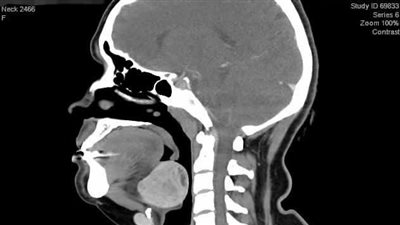

نجح فريق جراحة الأوعية الدموية بمستشفي المنيرة العام، فى إجراء عملية طارئة وذات مهارة خاصة لانقاذ حياة مريض، عبارة عن استئصال تمدد شرياني بالذراع لأحد مرضي الغسيل الكلوي.

وقال الدكتور أحمد حسن استشاري الجراحة العامة، إنه تم استئصال التمدد الشرياني بنجاح قبل حدوث أي مضاعفات كانت علي وشك الحدوث و أهمها النزيف أو الانفجار في حالة تعرض هذا التمدد لأي إصابة مباشرة.